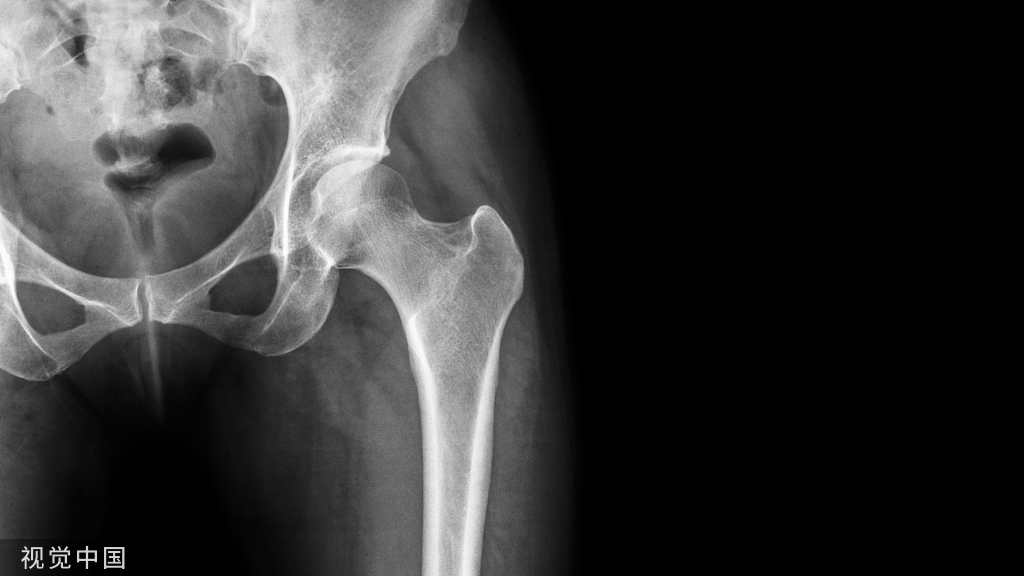

术后三周;外侧切口渗液流脓;血常规(+);ESR(+);CRP(+);细菌培养(+),拔出内固定冲洗引流。

几个问题1、腓骨固定必须吗?2、感染后行克氏针固定合适吗?3、从骨折走向感染性骨不连可以避免吗?4、目前患者有无临床不适?5、下一步怎么处理?